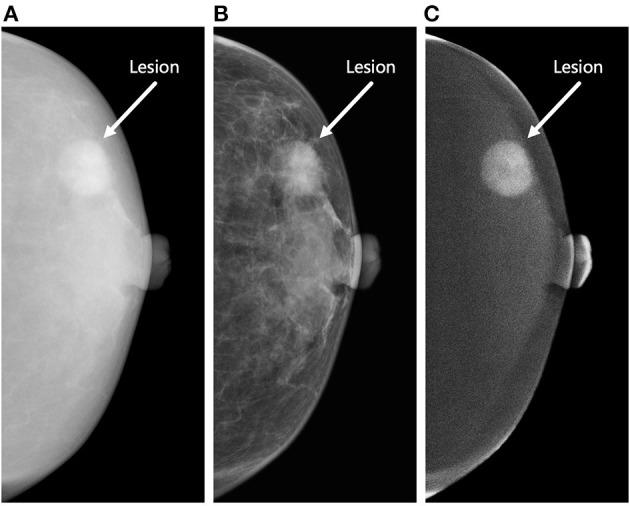

不同图像类型的对比增强乳腺摄影的放射组学分析:乳腺病变的分类

Radiomic Analysis of Contrast-Enhanced Mammography With Different Image Types: Classification of Breast Lesions.

A limited number of studies have focused on the radiomic analysis of contrast-enhanced mammography (CEM). We aimed to construct several radiomics-based models of CEM for classifying benign and malignant breast lesions. The retrospective, double-center study included women who underwent CEM between November 2013 and February 2020. Radiomic analysis was performed using high-energy (HE), low-energy (LE), and dual-energy subtraction (DES) images from CEM. Datasets were randomly divided into the training and testing sets at a ratio of 7:3. The maximum relevance minimum redundancy (mRMR) method and least absolute shrinkage and selection operator (LASSO) logistic regression were used to select the radiomic features and construct the best classification models. The performances of the models were assessed by the area under the receiver operating characteristic curve (AUC) with a 95% confidence interval (CI). Leave-group-out cross-validation (LGOCV) for 100 rounds was performed to obtain the mean AUCs, which were compared by the Wilcoxon rank-sum test and the Kruskal-Wallis rank-sum test. A total of 192 women with 226 breast lesions (101 benign; 125 malignant) were enrolled. The median age was 48 years (range, 22-70 years). For the classification of breast lesions, the AUCs of the best models were 0.931 (95% CI: 0.873-0.989) for HE, 0.897 (95% CI: 0.807-0.981) for LE, 0.882 (95% CI: 0.825-0.987) for DES images and 0.960 (95% CI: 0.910-0.998) for all of the CEM images in the testing set. According to LGOCV, the models constructed with the HE images and all of the CEM images showed the highest mean AUCs for the training (0.931 and 0.938, respectively; < 0.05 for both) and testing sets (0.892 and 0.889, respectively; = 0.55 for both), which were significantly higher than those of the two models constructed with the LE and DES images in the training (0.912 and 0.899, respectively; all < 0.05) and testing sets (0.866 and 0.862, respectively; all < 0.05). Radiomic analysis of CEM images was valuable for classifying benign and malignant breast lesions. The use of HE images or all three types of CEM images can achieve the best performance.

摘要

少数研究聚焦于对比增强乳腺钼靶摄影(CEM)的影像组学分析。我们旨在构建基于影像组学的CEM模型,用于对乳腺良恶性病变进行分类。这项回顾性、双中心研究纳入了2013年11月至2020年2月期间接受CEM检查的女性。使用CEM的高能(HE)、低能(LE)和双能减影(DES)图像进行影像组学分析。数据集按7:3的比例随机分为训练集和测试集。采用最大相关最小冗余(mRMR)方法和最小绝对收缩与选择算子(LASSO)逻辑回归来选择影像组学特征并构建最佳分类模型。通过受试者操作特征曲线(AUC)下的面积及95%置信区间(CI)评估模型性能。进行100轮留一法交叉验证(LGOCV)以获得平均AUC,并通过Wilcoxon秩和检验和Kruskal-Wallis秩和检验进行比较。共纳入192例患有226个乳腺病变的女性(101个良性;125个恶性)。中位年龄为48岁(范围22 - 70岁)。对于乳腺病变的分类,测试集中最佳模型的AUC分别为:HE图像0.931(95%CI:0.873 - 0.989),LE图像0.897(95%CI:0.807 - 0.981),DES图像0.882(95%CI:0.825 - 0.987),所有CEM图像0.960(95%CI:0.910 - 0.998)。根据LGOCV,用HE图像和所有CEM图像构建的模型在训练集(分别为0.931和0.938;两者均P<0.05)和测试集(分别为0.892和0.889;两者均P = 0.55)中显示出最高的平均AUC,显著高于用LE和DES图像构建的两个模型在训练集(分别为0.912和0.899;均P<0.05)和测试集(分别为0.866和0.862;均P<0.05)中的表现。CEM图像的影像组学分析对于乳腺良恶性病变的分类具有重要价值。使用HE图像或所有三种类型的CEM图像可实现最佳性能。